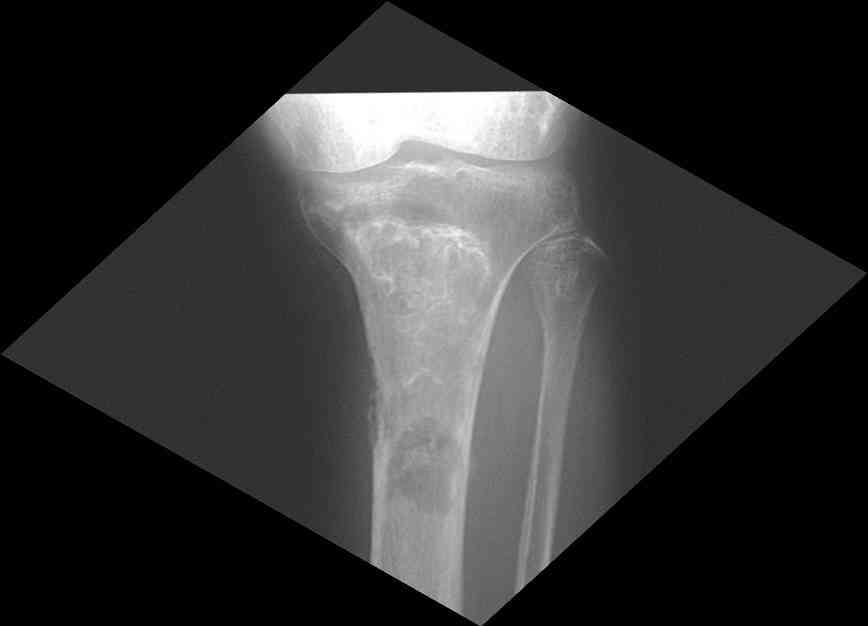

Представленные Вами данные о пациенте 57 дет с болезнью Альбертс-Шенберга чрезвычайно интересны, но диагноз вызывает большие сомнения. Для мраморной болезни характерно прееобладание склероза, а на представленных рентгенограммах преобладает симметричная дезорганизация архитектоники губчатой кости в эпиметафизарной зоне дистальных отделов бедер и голеней.

Мне кажется, представленные рентгенограммы скорее соответствуют варианту фиброзной дисплазии который был описан М. Campanacci (1976) или

обызвествляющей фиброме H.E.Schlitter (1958).

Уважаемый Константин Иванович! Полностью согласен с проф. Михайловым, данный случай не похож на мраморную болезнь, при которой имеется резкое, строго симметричное и генерализованное уплотнение костной ткани (остеопетроз), и кость оказывается построенной преимущественно из гомогенного компактного костного вещества. Для примера привожу случай из архива нашего института (бедренные, плечевые кости и таз, рис 1,2,3)

Изменения структуры костей у Вашего пациента больше похожи на полиоссальную форму фиброзной дисплазии или болезнь Педжета, возможены также инфаркты костного мозга б.берцовых костей. К сожалению, качество снимка не очень хорошее, непонятно, сохранен ли кортикальный слой б.берцовых костей по передней поверхности.

Для примера привожу случай из архива американской ассоциации рентгенологов (ACR) - развитие злокачественной фиброзной гистиоцитомы на левой б.берцовой кости у пациента с множественными инфарктами костного мозга (рис 4,5 - левая, рис 6 - правая)

Не являюсь специалистом по костной патологии, но мне кажется, на ренгенограмме множественные мета-диафизарные образования напоминяющее змееподобных извилистых линии и периостеальные ламинирование очень напоминяет картину остеонекроза (инфаркта) костей, возможно связано с длительным применением стероидов.

слайды из прошлегодного случая.